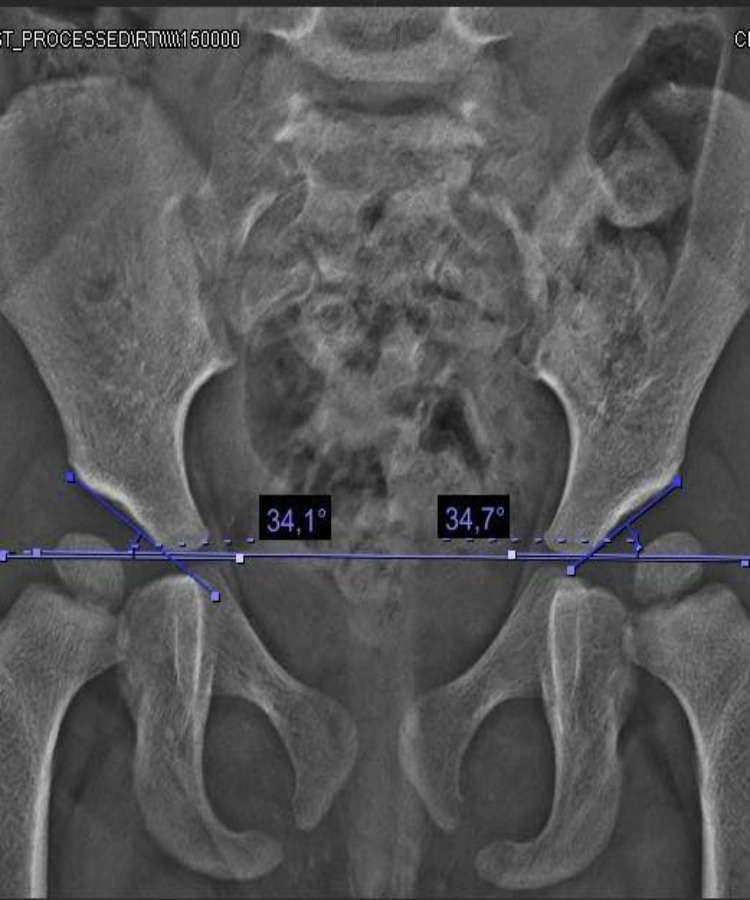

Las deformidades de pie y rodilla incluyen genu varo, genu valgo, pie plano y pie cavo, con causas congénitas o postraumáticas.